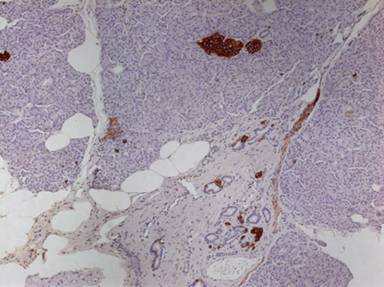

Figure 2. Ductuloinsular complex which is the hallmark of nesidioblastosis (immunohistochemistry synaptophysin, 20x). |

The pathological criteria for establishing its diagnosis are the presence of differently-sized islets and poorly defined endocrine cell clusters scattered in the acinar parenchyma and often intimately connected with small or large ducts (ductuloinsular complexes) [10]. In our case, vacuolated cells could be seen arising from the pancreatic ductal epithelium (Figure 1). On immunohistochemistry these cells were be identified to be neuroendocrine cells forming ductuloinsular complexes (Figure 2).